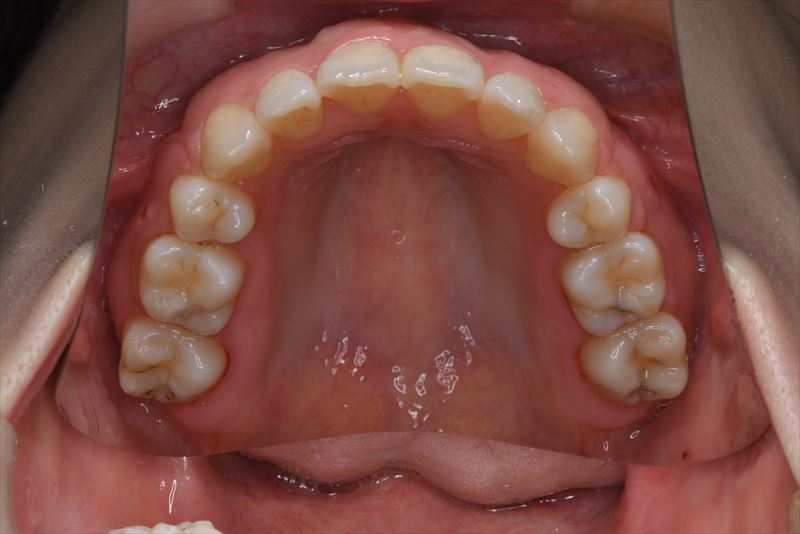

治療後

臼歯のみの咬合、口唇の閉鎖が難しい状況でした。抜歯を行い前歯を牽引することで、良好な側貌と緊密な咬合を獲得できました。